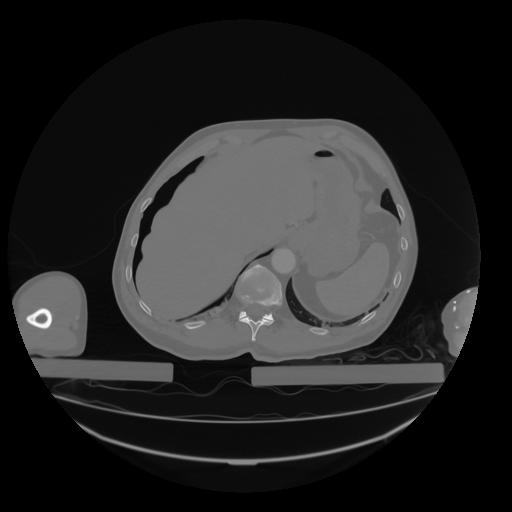

28 CUERPO,CE,Vol,2.0,CUERPO,,